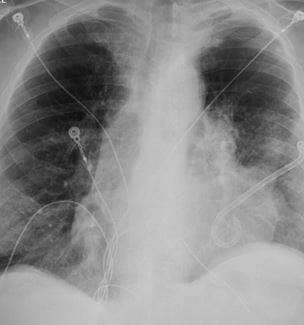

Digital Tomosynthesis Enhances Care in Patients with Emphysema

Benefits include less radiation and financial savings - Innovations in Pulmonology & Sleep Medicine | Summer 2023